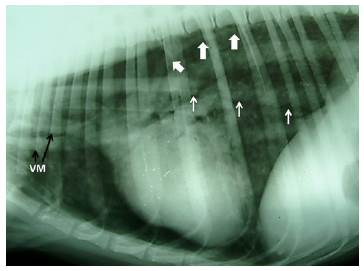

Al ingreso a consulta el paciente presentaba un estado de conciencia en depresión, con mucosas pálidas y cianóticas. La frecuencia cardiaca estaba incrementada (140 Ipm) y respiración abdominal marcada con posición ortopneica. A la auscultación no se lograron identificar los sonidos respiratorios con claridad. Sobre la base de la anamnesis y la exploración física se concluyó en un neumotórax bilateral. Se realizó un estudio radiográfico simple, comprobando el diagnóstico y denotando además la presencia de neumomediastino (Figura 1). Se administró oxígeno al 100% con mascarilla y se realizó una toracocentesis, obteniendo 500 cm3 de aire de ambos hemitórax, restituyendo la función pulmonar y mejorando clínicamente al paciente.